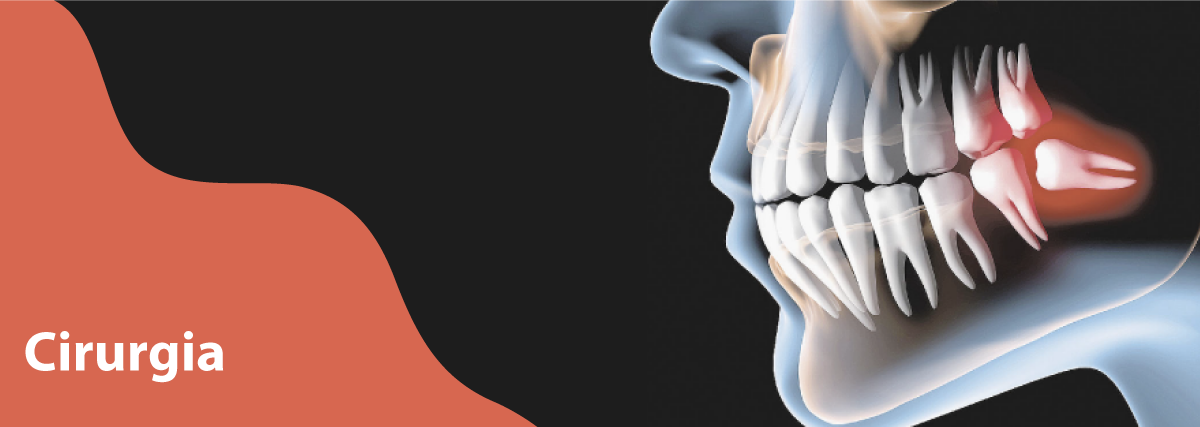

Cirurgia

Na maioria dos casos, são realizadas no consultório somente as cirurgias orais menores, por um especialista na área. A princípio os procedimentos menores incluem as exodontias (extração de dentes) exodontias de dentes não irrompidos, ou que ao se desenvolverem não se acomodaram na arcada devido a falta de espaço, que neste caso é necessário um exame mais detalhado do caso, como radiografias, ou mesmo tomografias computadorizadas para um melhor diagnóstico e planejamento cirúrgico. A remoção de cistos do complexo maxilo-mandibular, que são lesões que se desenvolvem dentro do osso e o expandem, contendo líquido no seu interior, desencadeado por diversas causas. Os tumores de pequenas proporções oriundos de glândulas salivares, aumento de volume nas gengivas, ou dos tecidos adjacentes. Correções cirúrgicas para adaptação de próteses, implantes osteointegrados, também compõe esta gama de cirurgias ditas menores.